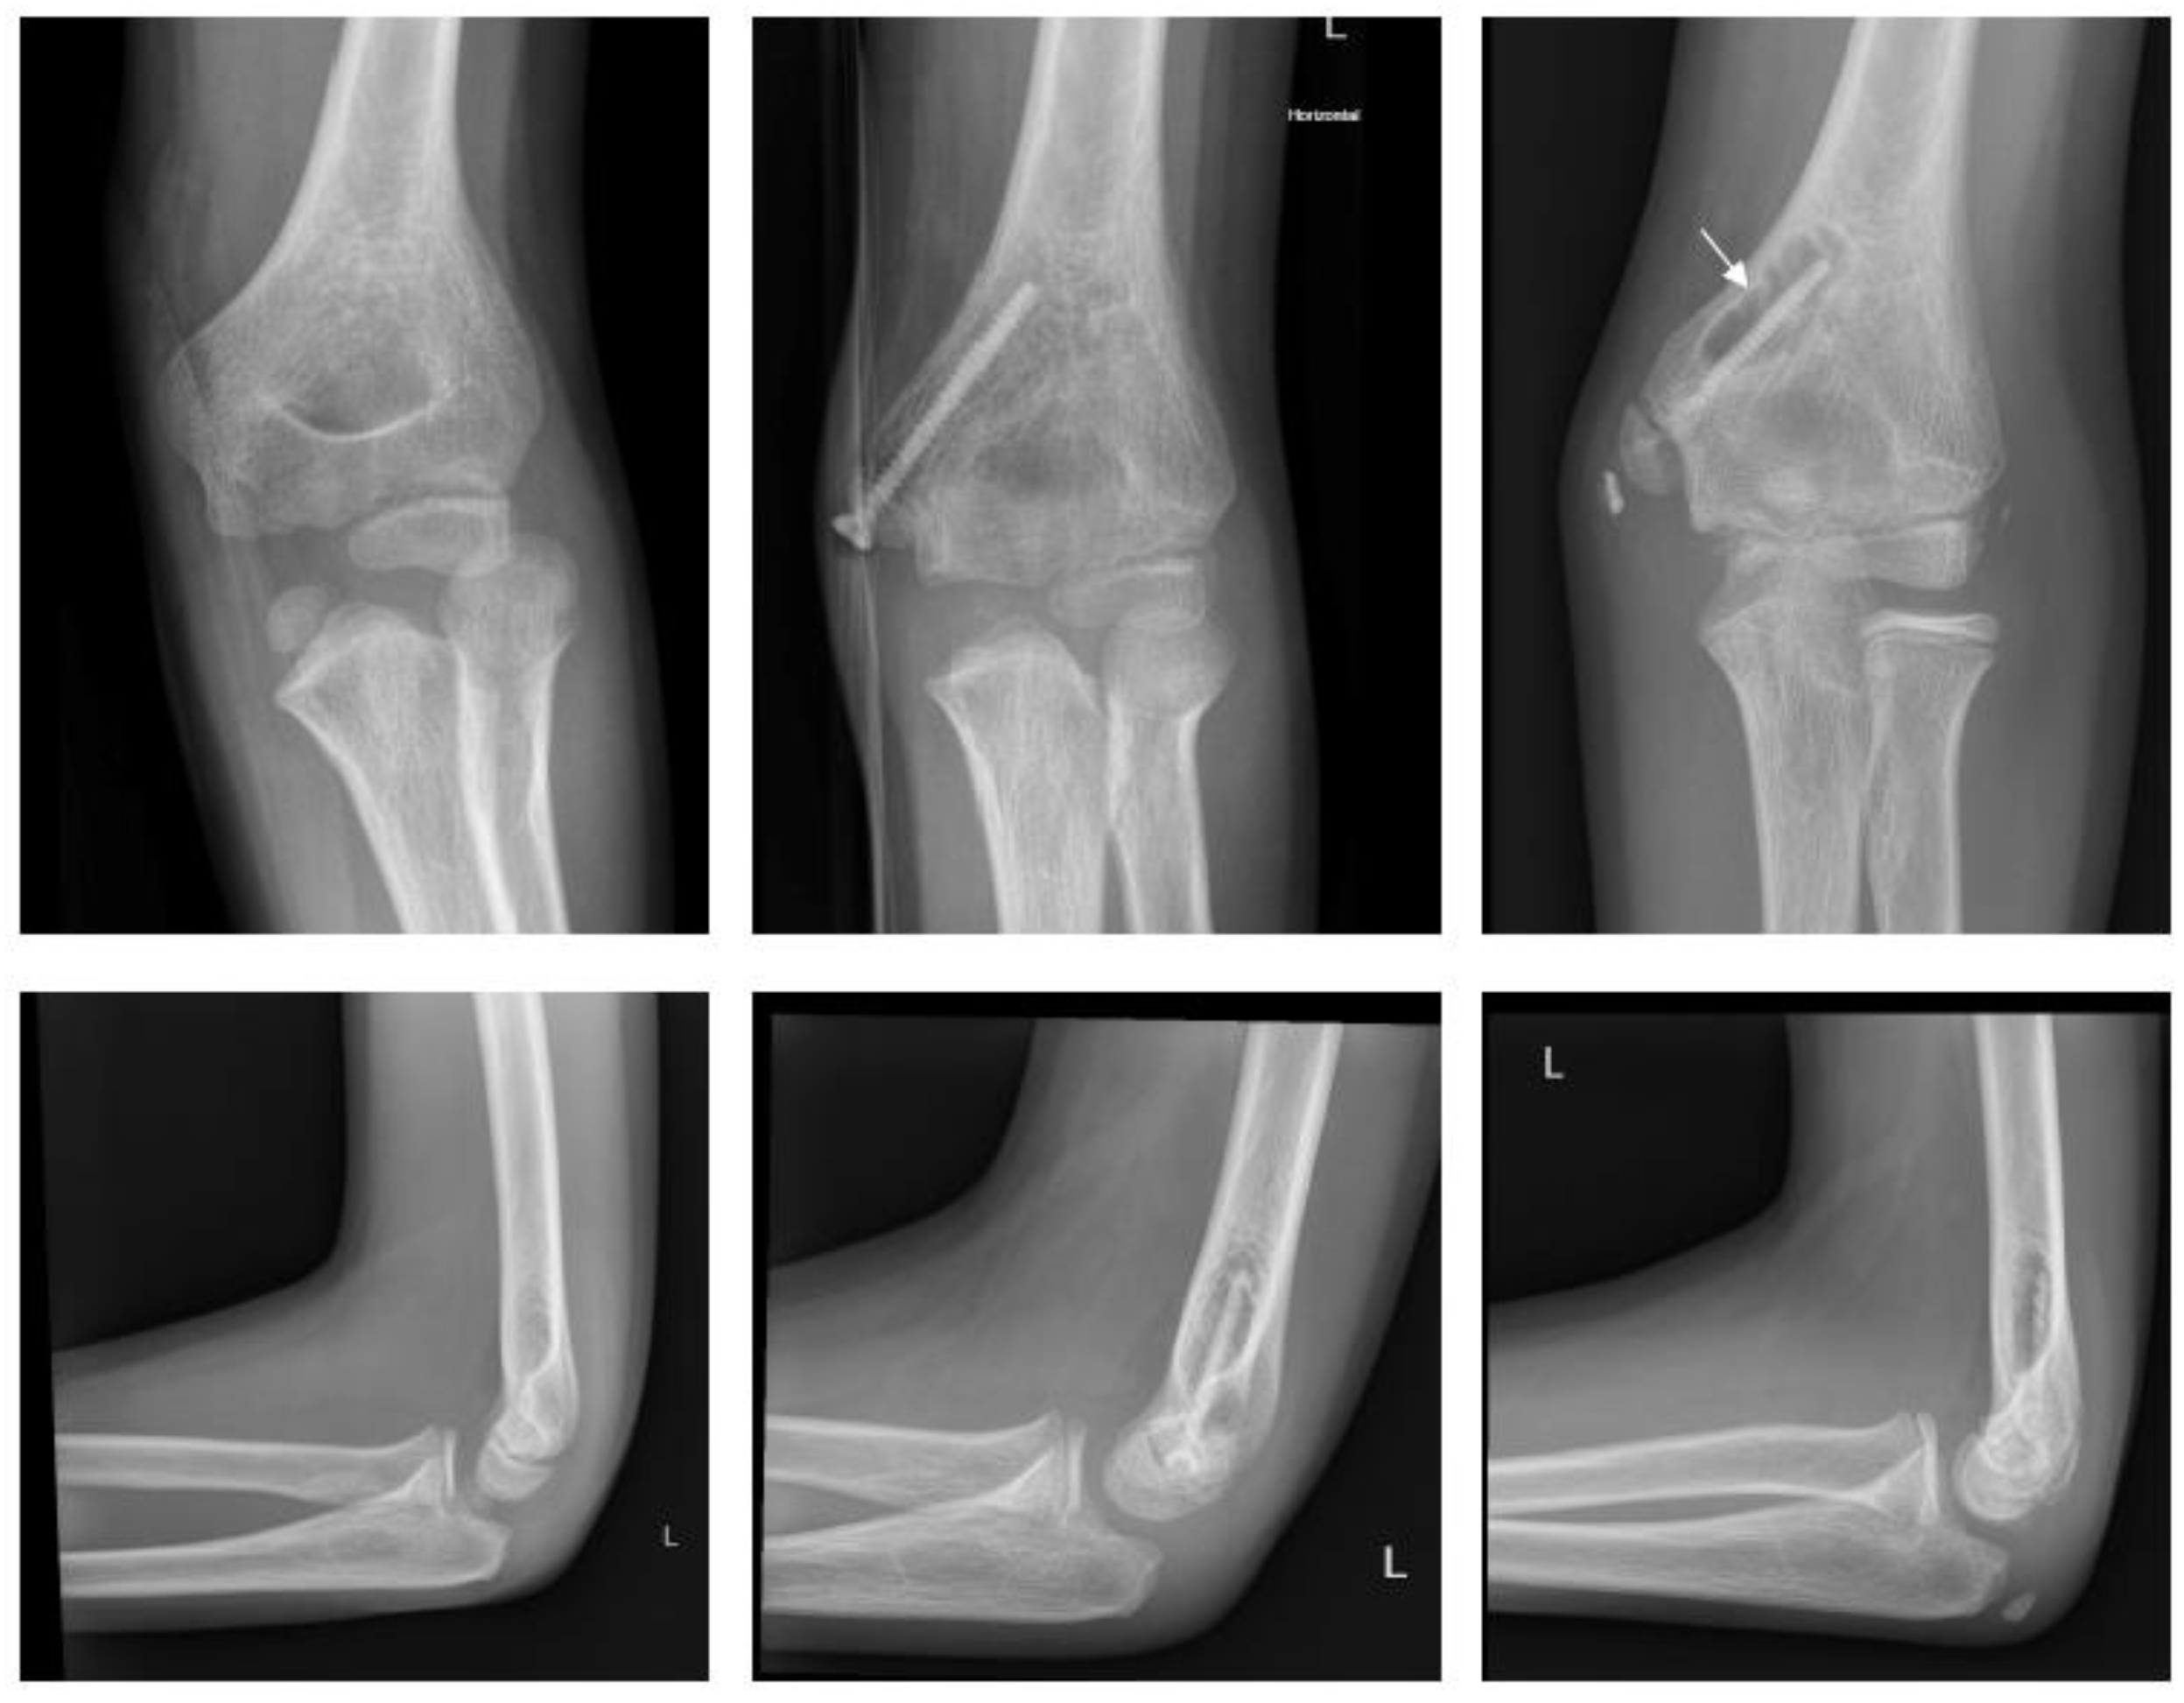

2.4.2. Fracture of the Medial Epicondyle